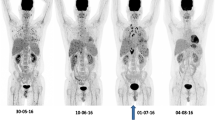

The overall agreement of all studies is that FDG-PET/CT is useful in staging IFIs. It has the advantage of being a whole-body imaging modality and is able to detect metastatic infectious foci, which are not detected by other imaging studies. This phenomenon was consistently demonstrated in a number of papers [49–51]. It will be helpful before the onset of therapy to know the extent of the infection and the organs involved, not only to correctly stage it during infection, but also to decide later if the infection disappeared and after completion to exclude recurrence of the fungal infection. An example of a patient (10-year-old girl) with disseminated fungal infection is shown in Fig. 3.

Example of use of FDG-PET in therapy monitoring in a 2-year-old girl with Langerhans cell histiocytosis and bone marrow transplantation. She was diagnosed (after biopsy) with aspergillus lesions in the liver. a Baseline FDG-PET scan, MIP image, revealing multiple fungal lesions in the liver. b FDG-PET scan after 6 months of antifungal therapy, showing decrease in uptake of some liver lesions, but increase of other liver lesions. Based on these findings, antifungal treatment was switched. c FDG-PET scan 3 months after therapy switch, revealing disappearing of all liver lesions expect one which became larger in time. Eventually this lesion was surgically removed, showing an encapsulated fungal lesion, which could not be reached by the antifungal drugs. Note also the decreased uptake in the brain at the third scan. This scan was performed under sedation

Role of FDG-PET in therapy monitoring of patients with IFIs

Several authors demonstrated the ability of FDG-PET in monitoring therapy of patients with IFIs [12, 52, 64, 65, 73, 80, 82, 84, 85, 92]. This is particularly crucial in disseminated and deep organ infection without fungemia. Some treatment protocols recommend that antifungal drugs should be given for a number of weeks in patients with suspected IFIs, also when blood cultures are negative. IFIs in immunocompromised patients are life threatening, and antifungal therapy is not only extensive, but must also be prolonged for a long time (depending on which fungal infection 6 months–2 years). In cases where there is no fungemia, the duration of therapy becomes ambiguous. In case of immunocompromised patients being evaluated for HSCT or SOT, it is important to know if all residual IFI are cleared before these procedures are undertaken. Clearly, it is of invaluable importance to have a noninvasive whole-body technique to localize all fungal lesions and to have a possibility to monitor disease activity to decide if therapy can be stopped, or should be prolonged or switched. In disseminated candidiasis, lesions seen on US, CT, or MRI have been found to persist for a long time after successful antifungal treatment due to, e.g., fibrosis and therefore these imaging modalities may have limited roles in assessing therapeutic effect and guiding therapy. FDG-PET will provide accurate information on therapeutic response especially for residual focal deposits in disseminated candidiasis. In one publication, FDG correctly predicted disease progression where MRI findings suggested improvement [12]. In another study, after completion of antifungal therapy for hepatosplenic and renal abscess before restarting chemotherapy, FDG-PET/CT detected lesions in the skeletal, cardiac muscles and the lungs showing antifungal treatment failure; hence, a different antifungal was given and lesions resolved [52].

Figure 4 shows the use of FDG-PET in clinical practice and how FDG-PET is important even with the development of several new diagnostic tests that are more sensitive than blood culture such as T2MR and T2Candida. These tests provide the clinician an idea of the presence of the fungi even at very low levels, but are not able to tell how the fungi in different lesions in the body respond to the antifungal therapy. As this figure clearly demonstrates, there was response of some liver lesions but also new lesions developed after 6 months of antifungal therapy. Based on this second FDG-PET scan in this 3-year-old girl, a new antifungal drug regimen was started. Three months after the start of this new treatment, most liver lesions responded completely leaving only one large lesion with a large necrotic center and increased peripheral metabolic activity. Eventually, this lesion was surgically removed and pathology indeed revealed an encapsulated fungal lesion. This different response of the different lesions illustrates how FDG-PET imaging is able to help in therapy decision making in children with IFIs.